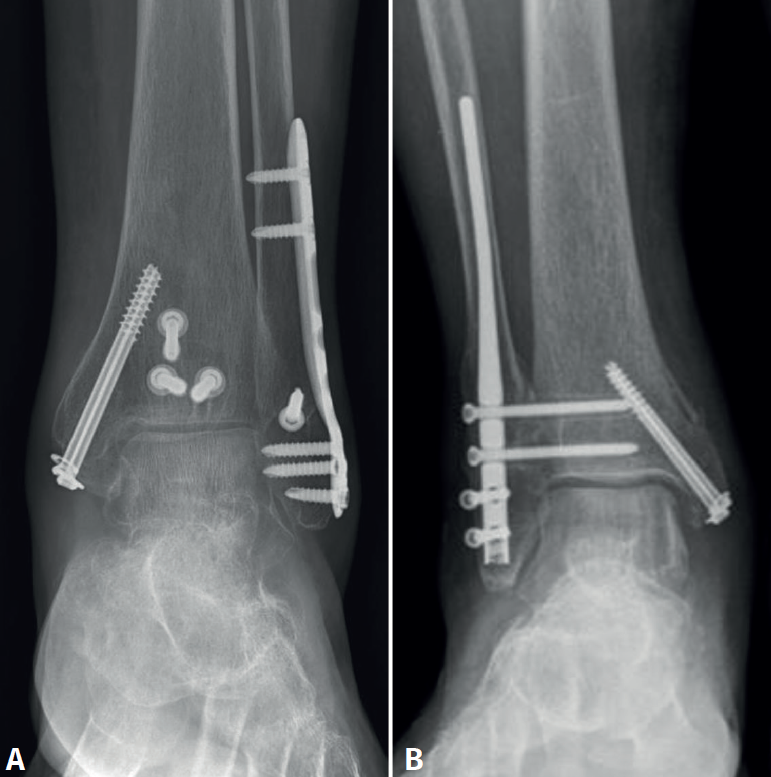

Por tanto, el objetivo de nuestro estudio es comparar los resultados funcionales y las complicaciones del tratamiento de las fracturas trimaleolares en pacientes mayores de 75 años con 2 métodos diferentes de tratamiento: RAFI y osteosíntesis con clavo intramedular de peroné (Figura 1).

Se recuperaron los datos de 126 pacientes, de los cuales se perdió el seguimiento de 42, por lo que la muestra final recabada fue de 84 pacientes. Se clasificaron en 2 grupos, uno de 52 pacientes (grupo 1), a los que se les realizó un abordaje posterior y una reparación “360” de todos los componentes de la fractura trimaleolar, y un segundo grupo de 32 pacientes (grupo 2) a los que se realizó una síntesis con un clavo de peroné intramedular de segunda generación, además de reparación del maléolo medial, sin abordar la fractura del maléolo posterior.